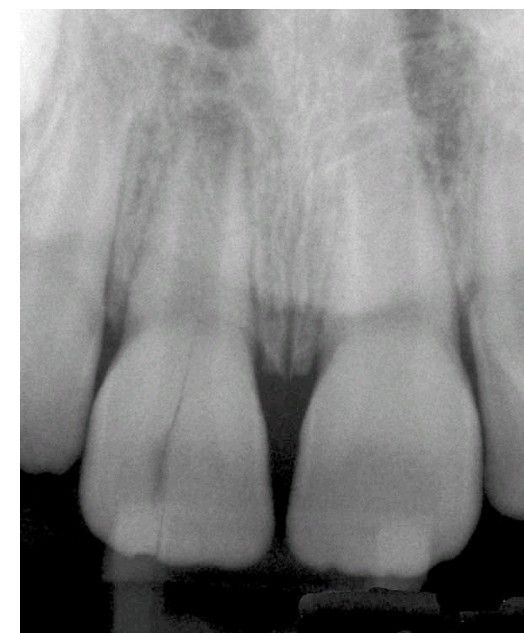

Vertical root fracture

Physical trauma from sports-related injuries or seizureinduced trauma, if directed accordingly, may cause a vertical root fracture in a tooth. This fracture occurred in a 7-year-old child secondary to trauma from a grand mal seizure.